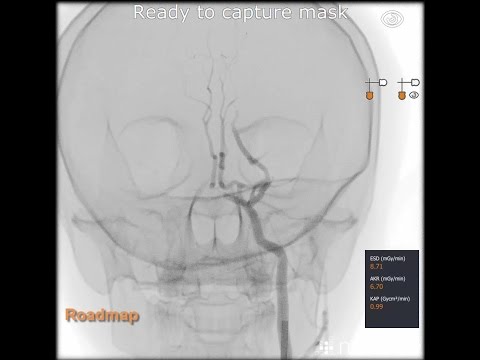

Hellow guys, Welcome to my website, and you are watching large Posterior communicating artery aneurysm - clipping. and this vIdeo is uploaded by 광주기독병원 신경외과 임준섭 at 2019-12-31T05:54:40-08:00. We are pramote this video only for entertainment and educational perpose only. So, I hop you like our website.